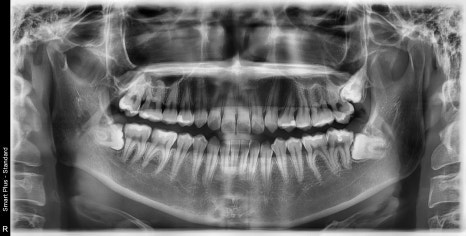

| 발치 전 | 발치 후 |